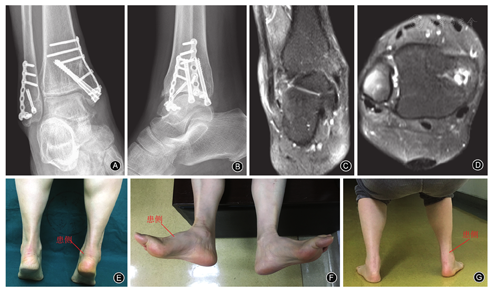

术后予头孢呋辛预防感染治疗3 d。术后2周伤口拆线;术后1个月拆除石膏,穿步行靴部分负重行走,允许患者踝关节背伸、跖屈锻炼,避免内翻、外翻活动;术后3个月全负重行走,恢复顺利。术后15个月复查右侧踝关节正、侧位X线片示骨折愈合良好,踝关节间隙正常(图2A,图2B)。患者日常活动不受限,行走活动时稍有僵硬不适,剧烈活动后稍有疼痛,美国足踝外科协会(American Orthopaedic Foot and Ankle Society,AOFAS)评分为92分。术后2年余复查右踝MRI示腓骨短肌腱连续性存在,冠状位及横断位可见轻微水肿高信号(图2C,图2D)。体格检查示双足提踵试验阴性(图2E),右足背伸、内翻、外翻活动度正常,与健侧相同(图2F),右足外翻肌力Ⅴ级,与健侧相同;患者下蹲不受限(图2G)。患者已恢复爬山运动,AOFAS评分为100分。